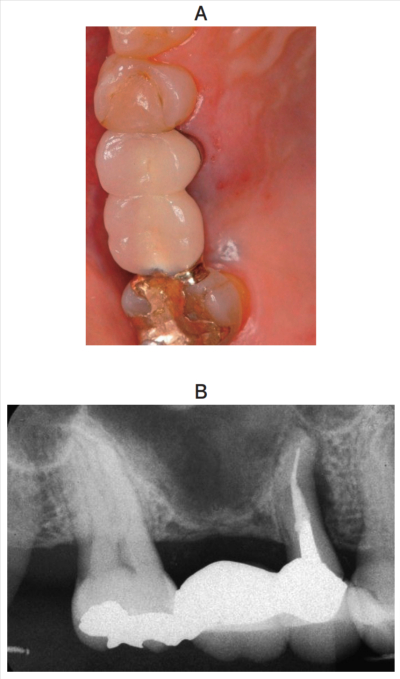

59歳の女性。上顎右側第二小臼歯の咬合痛を主訴として来院した。週前に違和感を自覚したがそのままにしていたところ、昨日から咬合痛があるという。初診時の口腔内写真とエックス線写真を別に示す。歯周組織検査結果の一部を表に示す。

原因として考えられるのはどれか。1つ選べ。

a. 歯根囊胞

b. 歯根破折

c. 骨性異形成症

d. 歯根外部吸収

e. 水平性食片圧入